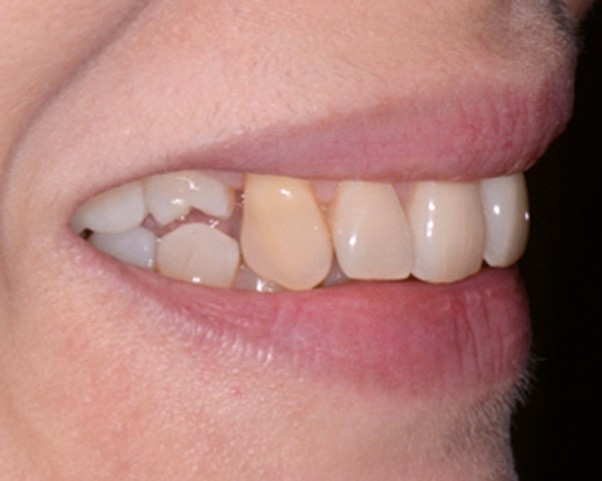

Sur les figures 1a et b, les trois étages de la face sont équilibrés. Le sourire met en évidence une légère bascule du plan d’occlusion.

Les muscles orbiculaires se contractent lorsque les lèvres sont jointives. Le sourire est spontané, large et les lèvres sont charnues. La courbe du sourire est satisfaisante de 12 à 22 puis les dents rentrent, disparaissent de face et apparaissent plus hautes sur le sourire de trois-quarts. Les incisives maxillaires sont bien placées par rapport à la lèvre inférieure (fig. 3).

Fig. 1 – Photographies exobuccales de face au repos (a) et lors du sourire (b), février 2016. Visage équilibré aux trois étages de même hauteur. Le sourire est…